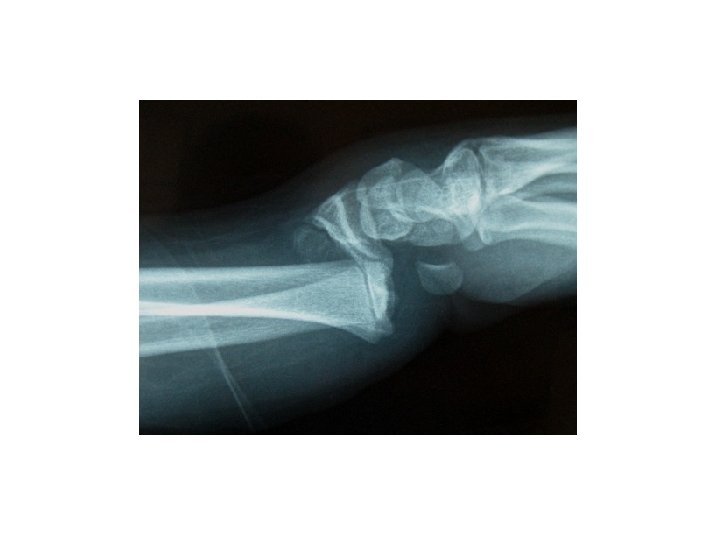

Describe types of displacement of fracture